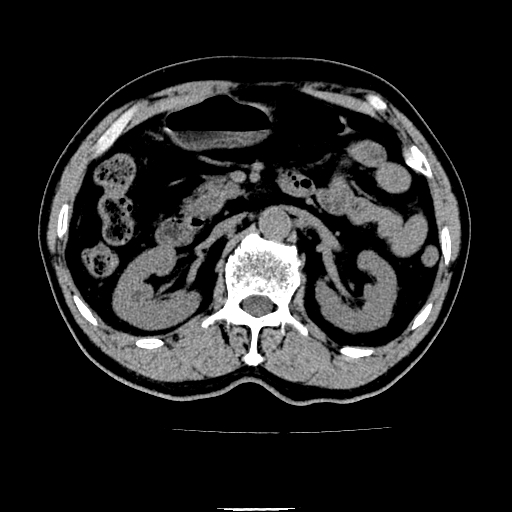

以下是引用chenqiong在2010-3-25 20:56:00的发言:[br]1、胆囊炎,胆囊息肉[br]2、肝内胆管及胆总管扩张,胆总管下端结石[br]3、十二指肠乳头旁憩室

以下是引用zxl51642在2010-3-26 10:47:00的发言:[br]胆囊炎,胆囊息肉,胆总管扩张,但未看到明显肿块,肝内胆管扩张不像恶性,炎性狭窄或阴性结石可能吧,建议mrcp,右肾小囊肿